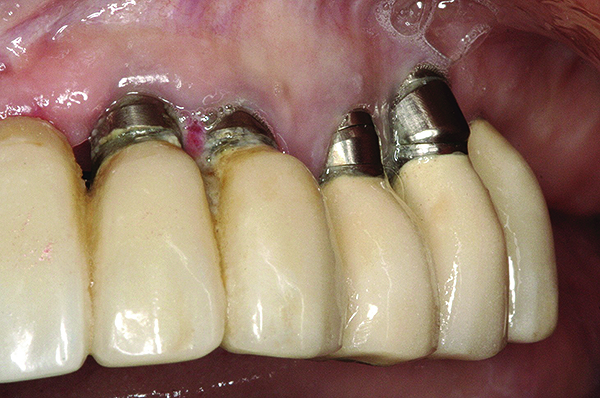

Fig 15. Clinical view of a 65-year-old female patient 5 years after insertion of a porcelain-fused-to-metal prosthesis on six threaded titanium implants in the maxilla (site Nos. 5, 7, 8, 10, 12, and 13). There is no clinically observable recession around the prosthesis or implants.

Figure 15

Fig 16 and Fig 17. Clinical photographs demonstrating bone loss and recession 20 years after prosthesis insertion. Initially the gingival margin covered the implant collars and threads. Fig 16: maxillary right; implants were placed at site Nos. 3 through 6. Fig 17: maxillary left; implants were placed at site Nos. 10 through 13.

Figure 16

Figure 17